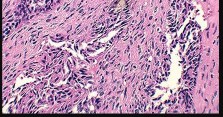

A 15-year-old boy presents with a permeative lytic lesion in the femoral diaphysis with aggressive periosteal reaction ('onion skinning'). Biopsy reveals uniform small round blue cells. Cytogenetic analysis of this tumor will most likely demonstrate which of the following translocations?

Explanation

The clinical and radiographic description is classic for Ewing sarcoma. The characteristic cytogenetic abnormality is a balanced translocation t(11;22)(q24;q12), which fuses the EWS gene on chromosome 22 with the FLI1 gene on chromosome 11. This is seen in approximately 85-90% of Ewing sarcomas. t(9;22) is the Philadelphia chromosome (CML), t(X;18) is seen in synovial sarcoma, t(2;13) in alveolar rhabdomyosarcoma, and t(12;16) in myxoid liposarcoma.